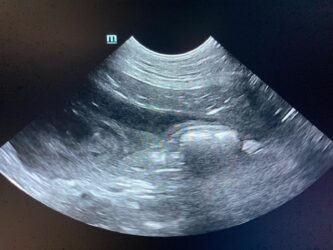

Dimitri, CV, 9.6kg, 11j, MC, bijgeruis 4/6 waarvoor hij vetmedin krijgt en opgevolgd wordt door cardioloog:

21/08/2025: Bij buurtcollega aangeboden voor hematurie. Plast vlot, op’t einde bloed te zien. Mevr. kookt zelf voor hem. Echo gehad + UOZ (geen idee hoe dit werd gecollecteerd) gedaan. Veel bloed in de…